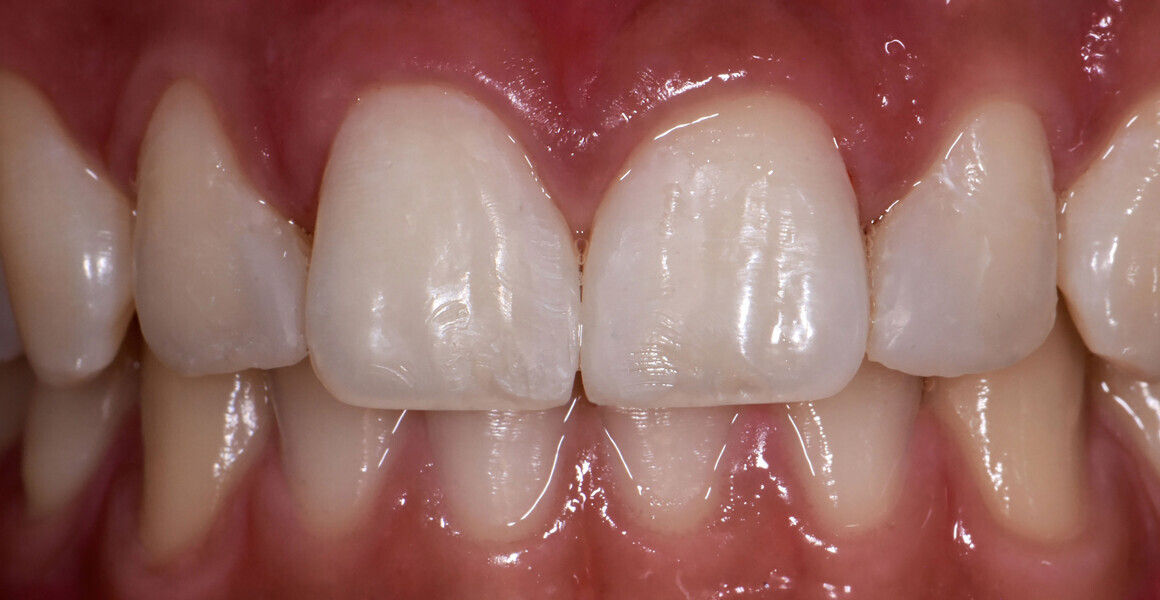

At the six-month follow-up appointment, the patient’s situation was very different to that at the initial consultation. There was proper closure of the interdental gaps and consequent formation of papillary tissue that harmonised the shape of the attached gingiva and of the reconstructed enamel perimeter (Figs. 18–21). In addition, the examination showed no fractures of the restoration or wear, no marginal discoloration or other staining, adequate marginal seal, adequate colour stability and translucency, very good surface structure and anatomical shape, excellent contact points, very good integrity of the teeth and no inflammation.

Fig. 20: Aesthetic result achieved.

Fig. 21a: Six-month follow-up.

Fig. 21b: Six-month follow-up.

Fig. 21c: Six-month follow-up.